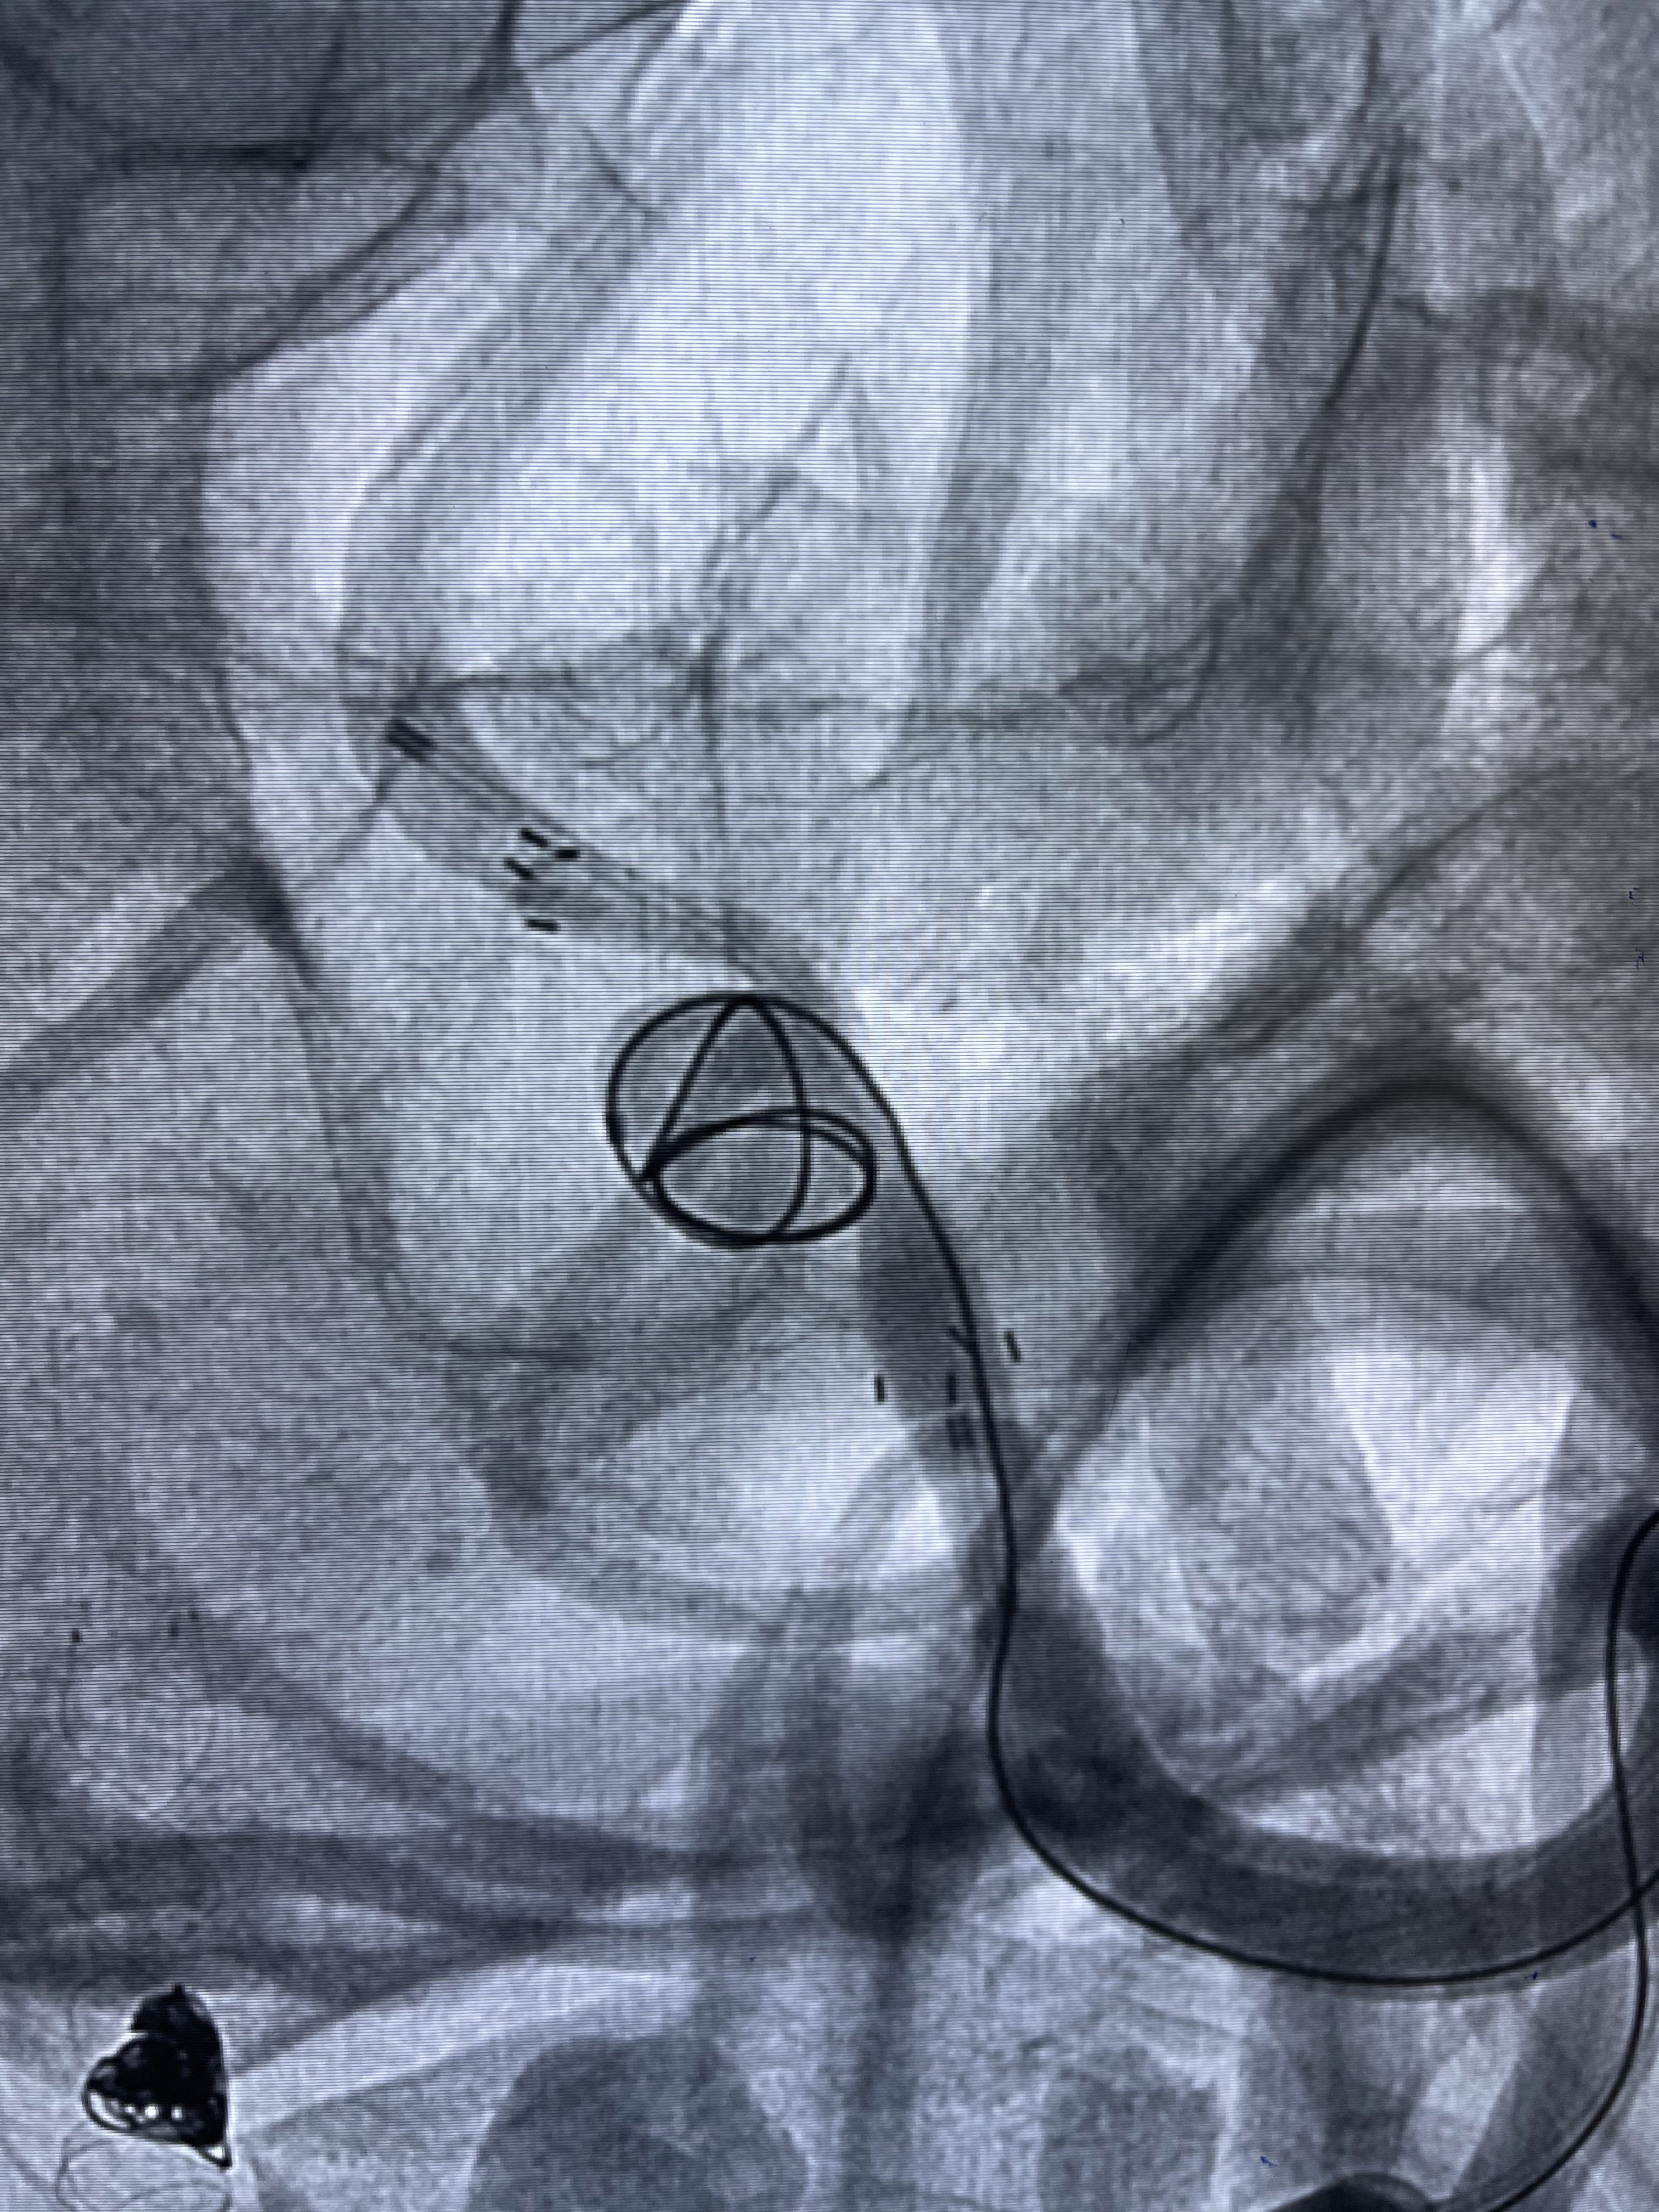

工作角度造影

8mm-40cm微弹簧圈成篮